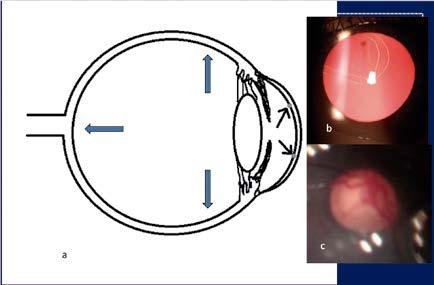

Aplicación clínica: Un desafío en la práctica real

Presentamos el caso de una paciente de 81 años con agudeza visual de ‘cuenta dedos’ en el ojo derecho y antecedente de trabeculectomía, cuya ampolla filtrante superior se encontraba funcional, pero marcadamente adelgazada (Figuras 1 y 2).

A la exploración, destacaba una catarata hipermadura, PIO de 9 mmHg y daño glaucomatoso avanzado (copa/disco 0.9).

La estrategia quirúrgica se definió mediante la microscopia especular y la UBM: un RCE crítico de 997 células/mm² (Figura 3) y un cristalino de gran diámetro anteroposterior con lens vault aumentado (Figura 4).

Figura 1. Catarata hipermadura

Figura 2. Ampolla filtrante avascular y adelgazada

Figura 3. Microscopia especular preoperatoria

Figura 4. UBM mostrando catarata con aumento del diámetro AP y del lens vault

Ante este escenario, donde la dureza nuclear y la estrechez del espacio de maniobra hacían de la facoemulsificación una opción de alto riesgo para el endotelio, se optó por una MSICS con abordaje temporal para minimizar el riesgo endotelial y proteger la ampolla filtrante superior. Se confeccionó un túnel escleral de 7 mm para una extracción del núcleo sin estrés mecánico (Figura 5). Se implantó una lente intraocular de tres piezas bajo viscoelástico y se aseguró la hermeticidad con un único punto corneoescleral (Figura 6).

El resultado postoperatorio validó la elección de la técnica. La paciente alcanzó una mejoría visual significativa, pasando de cuenta dedos a 20/40. En el seguimiento, se observó la lente centrada, el túnel sellado y una PIO estable de 9 mmHg (Figura 7A). La ampolla filtrante permaneció funcional y sin cambios morfológicos respecto al estado preoperatorio (Figura 7B).

Figura1. El incremento de presión intraocular en ojos pediátricos puede producir una expansión de los tejidos intraoculares (a), con estrías de Haab (b) y excavación del nervio óptico.